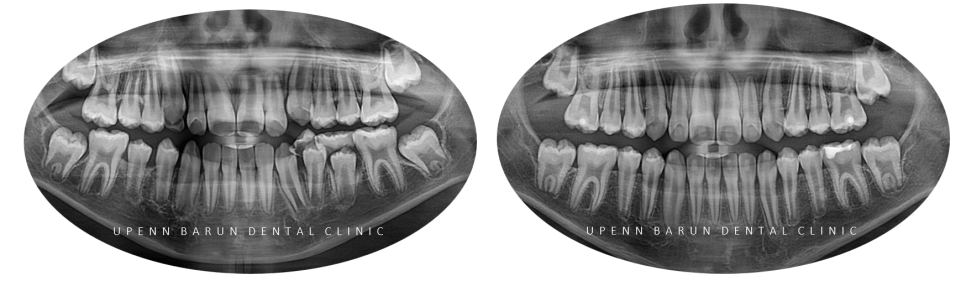

왼쪽 아래(#36) 영구치 충치 엑스레이 및 구내 포토

교정을 시작하기에 앞서

엑스레이를 확인해 보니 충치가 생겨

충치치료를 마무리하고 교정을 진행해드렸습니다 :)

충치를 제거해보니 생각보다 범위가 컸지만

보존적인 치료를 추구하는 유펜바른치과에서

레진치료로 마무리 해드렸습니다 :)